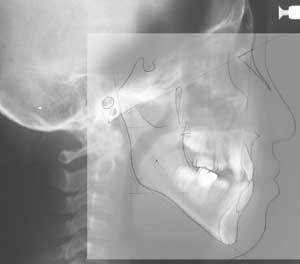

頭部X線規格写真(セファログラム)

X線の光源と被写体(人物)およびフィルム面までの距離が一定の条件の下に規格されており、同じ条件で客観的に本人と正常者との比較あるいは本人の経時的変化 (成長変化や治療による位置の変化)を比較することができます。

トレースの施行

レントゲンフィルムを正確にトレースします。

トレース図

この図には計測ポイントが定められており、距離や角度を計測するのに用いられます。それらの計測項目は性別や年齢に応じてあらかじめ正常値と正常範囲が判っているので、それらと比較することで、患者様の骨格や歯の位置や方向が、正常に対してどんな相違があるかを知ることができます。 具体的にはコンピュータを用いて専用のソフトで線形角度分析を行い正常値との比較を行い、以下のポリゴン表とプロフィログラムを作成します。当院では市販のソフトではなく、大学勤務時代に独自に開発した分析ソフトを用いています。